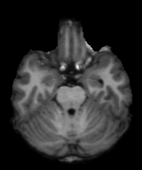

HCP Brain MRI We train on 1076 brain-extracted T1w images from the HCP dataset [24] and test on a sample of 100 pairs between 36 images via mean Dice over 28 midbrain structures [20, 21]. We train and execute the network at [130155130], then compute the Dice score at full resolution.

OASIS Brain MRI We use the OASIS-1 [12] data preprocessed by [9]. This dataset contains images of 414 subjects. Following the data split in [14], we train on 255 images and test on 153 images555Due to changes in the OASIS-1 data, our test set slightly differs from [14]. We evaluate all methods using our testing protocol so that results are consistent.The images in the dataset are of size [160192224], and we crop the center of the image according to the preprocessing in [14], leading to a size of [160144192]. During training, we sample image pairs randomly from the train set. For evaluation, we randomly pick 5 cases as the fixed images and register all the remaining 148 cases to the 5 cases, resulting in 740 image pairs overall.